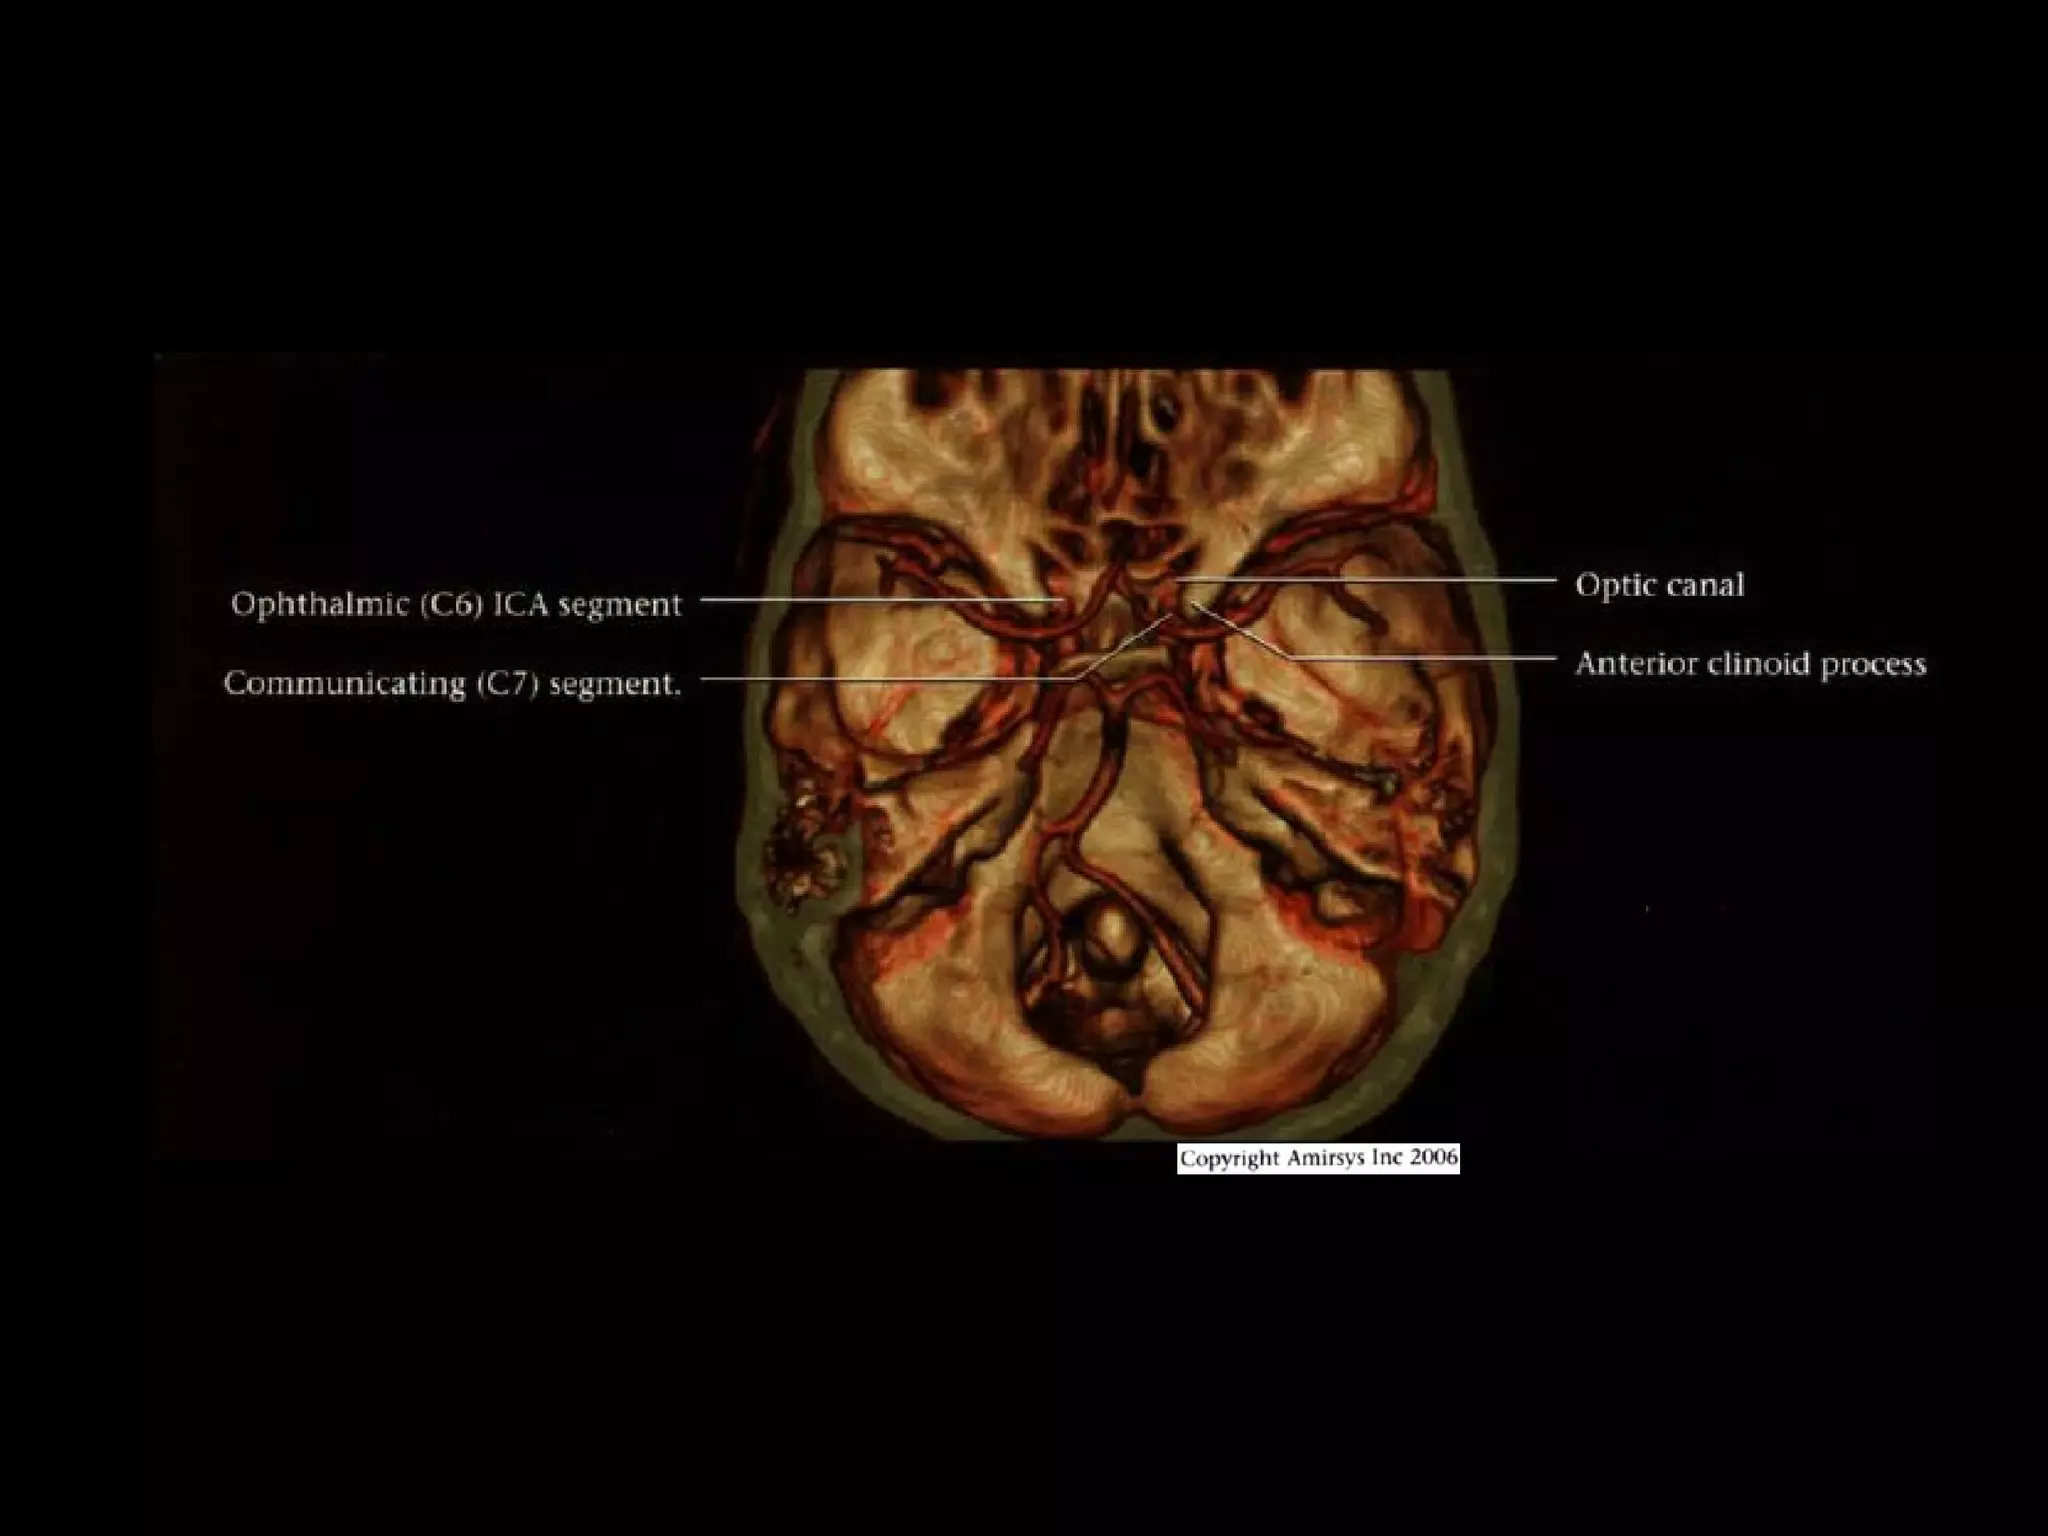

Ophthalmic (C6) segment

• Extends from distal dural ring at superior clinoid

to just below posterior communicating artery

(PCoA) origin

• Two important branches

- Ophthalmic Arteries (originates from

anterosuperior ICA, passes through optic canal

to orbit; gives off ocular, lacrimal, muscular

branches; extensive anastomoses with ECA)

- Superior hypophyseal artery (courses

posteromedially; supplies anterior pituitary,

infundibulum, optic nerve / chiasm)

Communicating (C7) segment

• Extends from below PCoA to terminal lCA bifurcation

into anterior cerebral artery (ACA), middle cerebral artery

(MCA)

• Passes between optic (CN2), oculomotor (CN3) nerves

• Major branches

- Posterior communicating artery

- Anterior choroidal artery (courses posteromedial,

then turns superolateral in suprasellar cistern; enters

temporal horn at choroidal fissure; supplies choroid

plexus, medial temporal lobe, basal ganglia,

posteroinferior internal capsule)